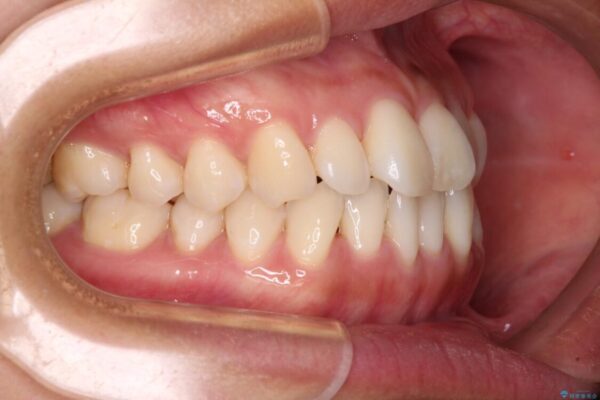

前歯のデコボコで前方に出ていることを気にして来院された患者様です。

上顎前歯が捻れて前方に飛び出しており、下顎前歯もそれに沿うようにデコボコとなっていました。

IPR(歯と歯の間を削る処置)によりスペースを獲得して上下顎前歯のデコボコを改善し、飛び出している前歯が引っ込むように設定し、インビザラインにて矯正治療を行うこととしました。

• 【モニター】前歯のデコボコをインビザラインで改善 治療前画像